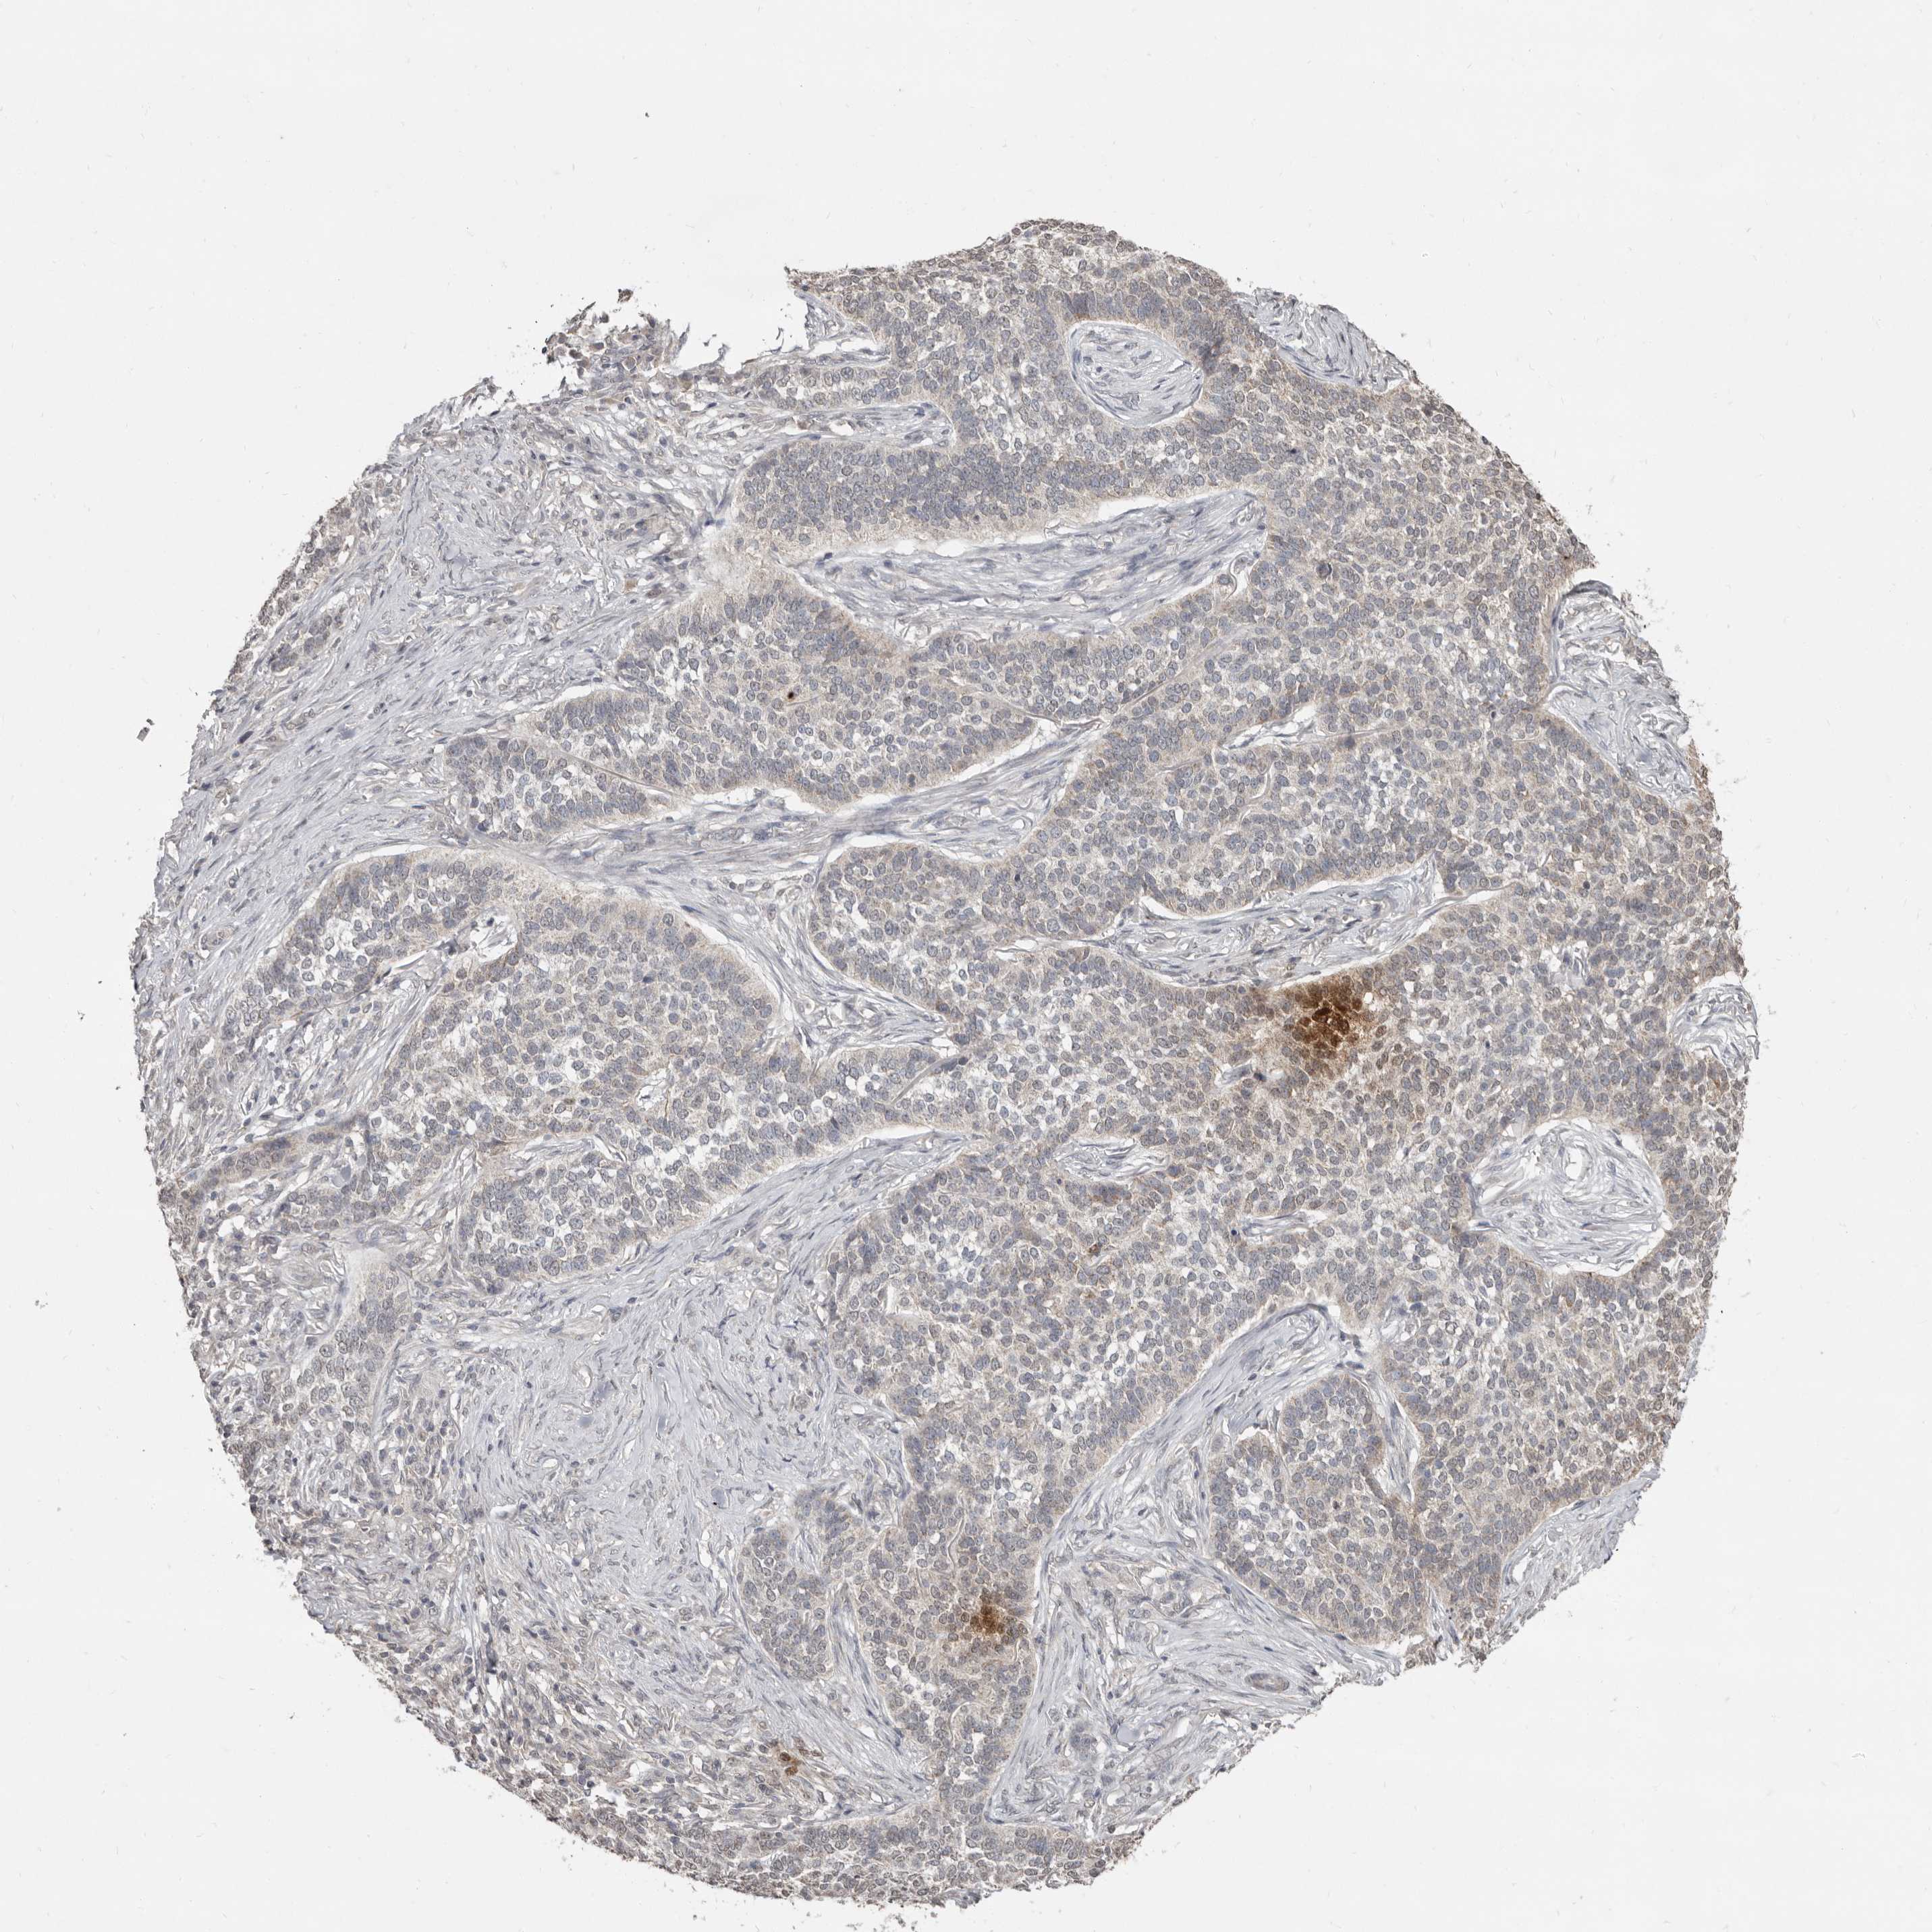

CANCER SKIN CANCER Show tissue menu

SKIN CANCER - Protein expressioni

A mouse-over function shows sample information and annotation data. Click on an image to view it in a full screen mode. Samples can be filtered based on level of antibody staining by selecting one or several of the following categories: high, medium, low and not detected. The assay and annotation is described here.

Each image is clickable and will lead to virtual microscopy that enables deeper exploration of all samples and also displays staining intensity scores, fraction scores and subcellular localization as well as patient and tissue information for each sample.

Antibody HPA016633

Squamous cell carcinoma in situ, NOS

Squamous cell carcinoma, NOS

Squamous cell carcinoma, metastatic, NOS

Basal cell carcinoma

Adnexal tumor, benign